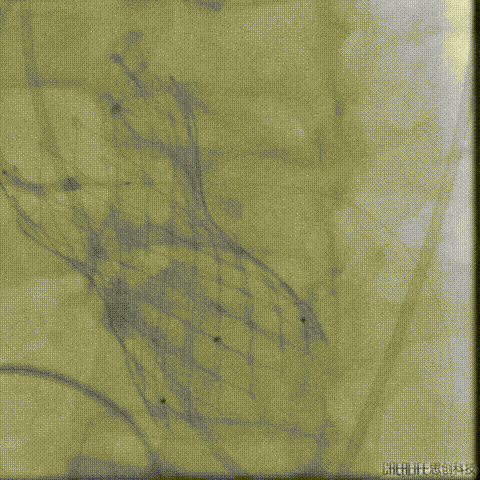

置入4.0mm*23mm微创冠脉支架

定位并释放支架

退出球囊扩张突入瓣架部位

复查冠脉造影

多体位复查冠脉造影